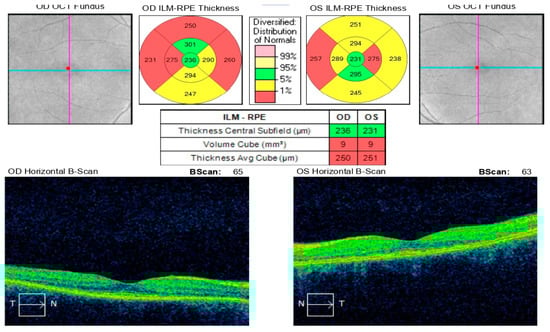

Optical coherence tomography (Topcon 3D OCT-2000) of the left macula revealed separation of the neurosensory retina from the retinal pigment epithelium, associated with alterations in the pigment epithelial layer and increased choroidal thickness (Figure 2).

One month after treatment initiation, resorption of the retinal edoema in the left eye was observed on OCT (Figure 5), accompanied by improvement in visual acuity and normalization of visual field parameters (Figure 6).

Figure 2. Analysis protocol of optical coherent tomography—Topcon 3D OCT-2000 of the macula of the left eye, showing separation of the neurosensorium from the underlying pigment epithelium with changes in the pigment layer.

Figure 5. CT (Topcon 3D OCT-2000) of the left macula showing edoema resolution.